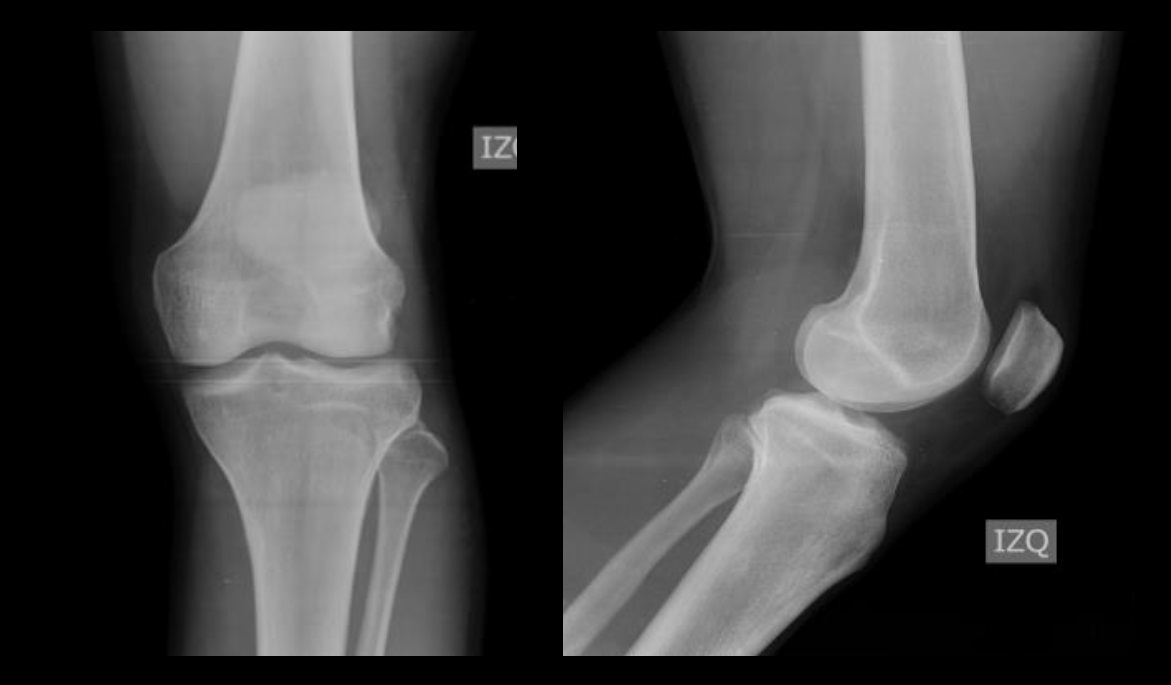

Luxación traumática aguda de la articulación tibioperonea proximal. Reporte de un caso y revisión bibliográfica. [Acute traumatic dislocation of the proximal tibiofibular joint: case report and review of the literature].